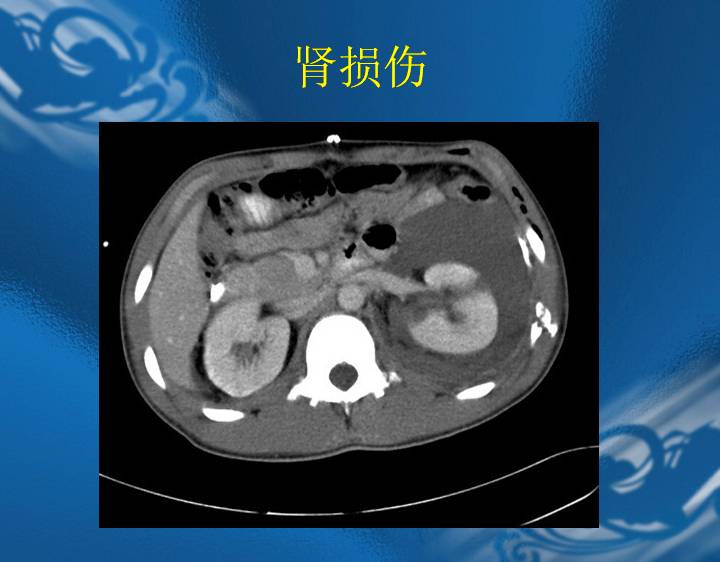

执业医师资格考试“实践技能”影像学辅导资料